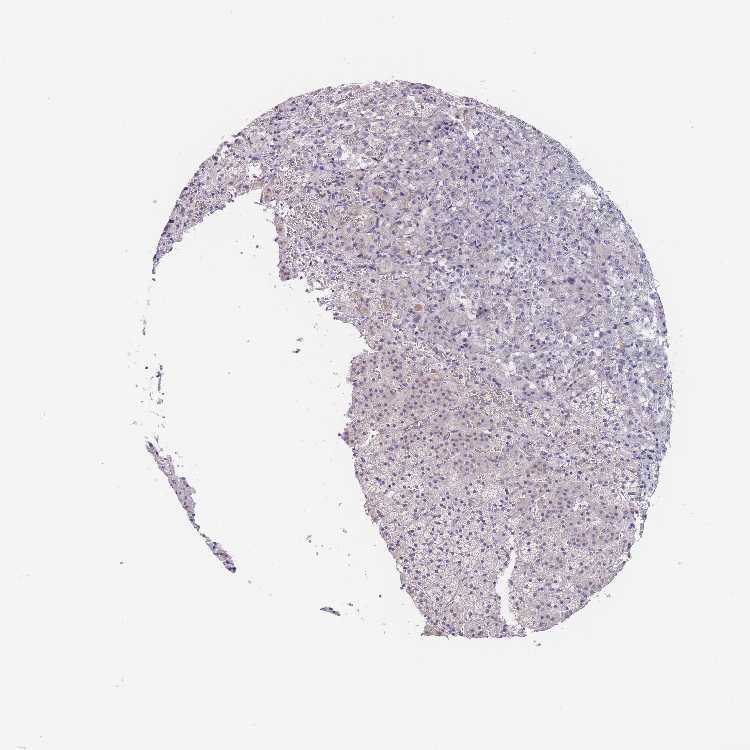

ADRENAL GLAND - Antibody stainingi

Antibody staining in the annotated cell types in the current human tissue is reported as not detected, low, medium, or high, based on conventional immunohistochemistry profiling in selected tissues. This score is based on the combination of the staining intensity and fraction of stained cells.

Each image is clickable and will lead to virtual microscopy that enables deeper exploration of all samples and also displays staining intensity scores, fraction scores and subcellular localization as well as patient and tissue information for each sample.

Antibody HPA049809

Glandular cells Not detected